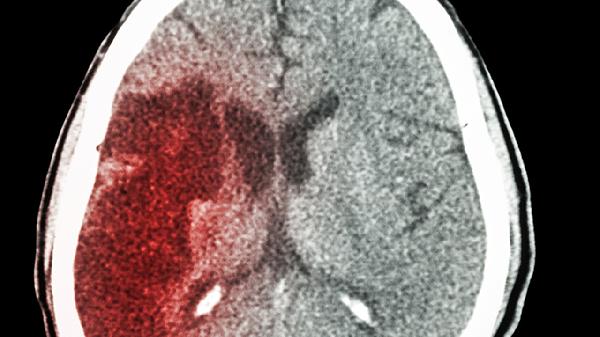

55岁女子血脂7.2,毫不在意,结果突然中风!医生:3错误害了她

55岁王阿姨最近总感觉头晕眼花,以为是更年期症状没在意。直到有天晨练时突然栽倒在地,送医检查才发现血脂高达7.2mmol/L!主治医师摇头叹息:"这三个习惯再不改,血管迟早要堵死..."